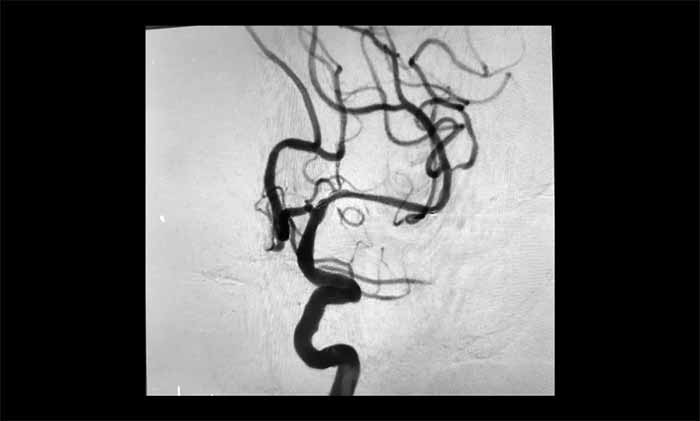

近日,一位70多岁患者因反复出现右侧肢体无力、言语含糊、口角流涎,被诊断为左侧大脑中动脉完全闭塞。他还合并颈内动脉动脉瘤、椎动脉狭窄等复杂问题,手术难度极高。其中,左侧大脑中动脉M1段的慢性完全性闭塞,是导致其神经功能缺损反复加重的主要原因。

席刚明教授、王贵平博士团队经过全面评估,最终在全麻下精细操作,利用微导丝穿过闭塞段,并以“球囊扩张+支架置入”完成血管再通,为患者打通这条关键的“生命线”。术后患者血流通畅,恢复良好。

▲ 左侧大脑中动脉完全闭塞

▲ 左侧大脑中动脉顺利开通